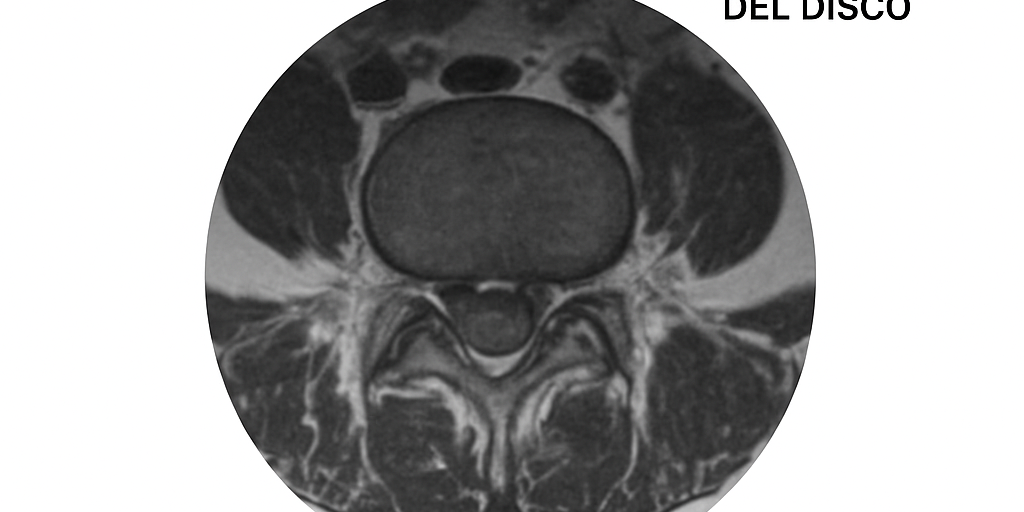

Pues bien, eso es justo lo que demuestra un estudio científico publicado en AJNR (American Journal of Neuroradiology), donde un equipo de investigadores revisó imágenes de resonancia y tomografías de más de 3.000 personas sin dolor de espalda, y los resultados son, simplemente, reveladores.

El estudio muestra que la mayoría de personas sin dolor alguno presentan signos de degeneración en sus discos intervertebrales. Por ejemplo:

Degeneración del disco: presente en el 37% de los individuos de 20 años y en el 96% de los de 80 años.

Protuberancia discal: del 30% a los 20 años al 84% a los 80 años.

Protrusión discal: del 29% a los 20 años al 43% a los 80 años.

Fisura anular: del 19% a los 20 años al 29% a los 80 años.